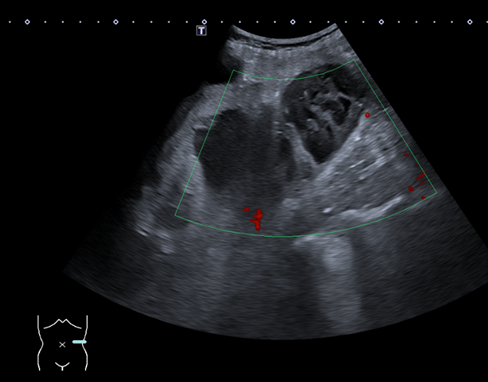

Ante la persistencia de los síntomas, se realiza ecografía en Atención Primaria, identificándose una lesión ovalada de unos 9 cm adyacente al riñón izquierdo, heterogénea, con áreas quísticas y sin flujo Doppler. La revisión de imágenes antiguas revela un quiste simple de gran tamaño en la misma localización, por lo que se sospecha complicación del mismo. Se deriva a Medicina Interna para estudio.